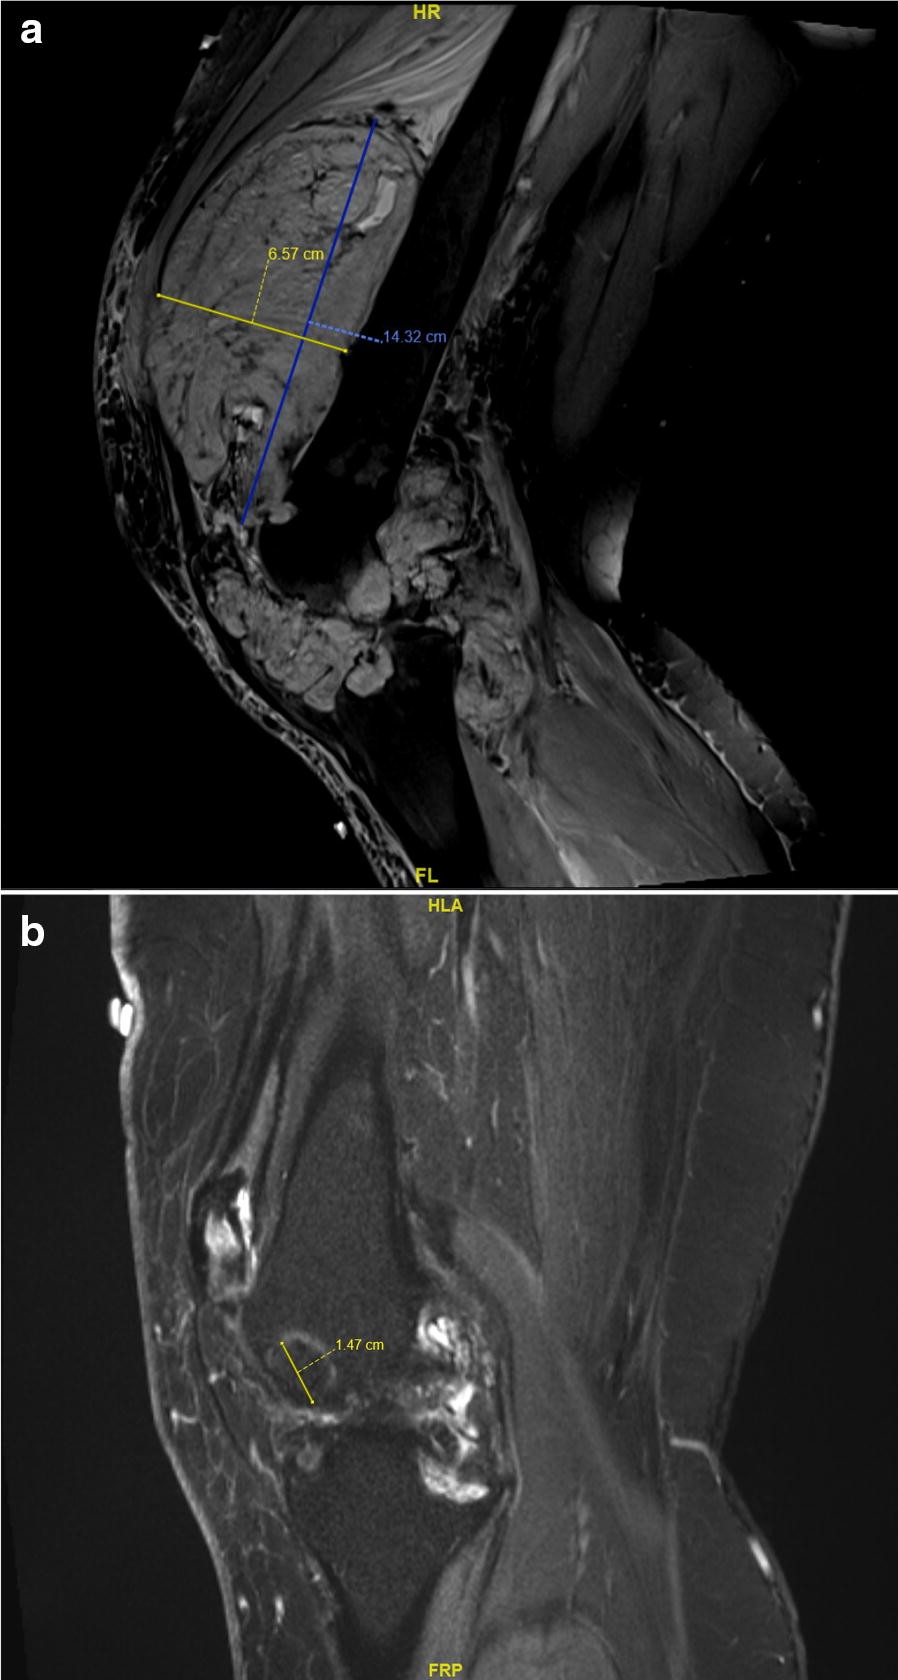

Fig. 1From: Tenosynovial giant cell tumor: case report of a patient effectively treated with pexidartinib (PLX3397) and review of the literatureMRI scan of suprapatellar aspect in January 2013 (a) and May 2017 (b)Back to article page